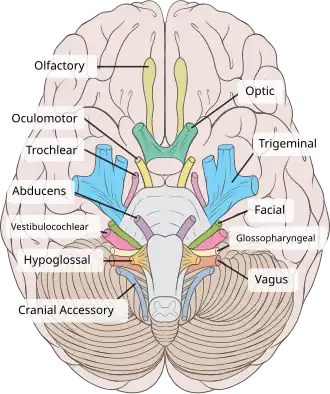

Tolosa-Hunt Syndrome is highly impacted by the inflammation of the cranial nerves, especially those that are located around the cavernous sinus. These include:

Ocular Motor Nerves[8]

- Oculomotor Nerve (Cranial Nerve III) is important for eye coordination and movement. These include saccades, eye tracking, and eye fixations. This impacts 80% of patients.

- Abducens Nerve (Cranial Nerve VI) helps with moving eye muscles. Individuals can move their eyes left and right. Patients have been reported to have an impact on this nerve at least 70% of the time.

- Trochlear Nerve (Cranial Nerve IV) helps move the eye muscles downward and upward and is impacted in patients 29% of the time.

In some cases, inflammation can also impact other cranial nerves. These include:

Sensory Nerves (trigeminal nerves)[8]

- Ophthalmic branch of the trigeminal nerve (V1). This nerve is important for the forehead, eye, and upper nose. Seems to be impacted 30% of the time.

- Maxillary branch of the trigeminal nerve (V2), which is important for sensing cheeks, upper lip, and upper teeth, is occasionally impacted.

- Mandibular branch of the trigeminal nerve (V2), which impacts sensation to the lower part of the face, such as the jaw, part of the teeth, and the ability to chew, is also occasionally affected.

A recent study involving a 14-year-old boy showed that the seventh cranial nerve has also been impacted, but not much is known about this one as compared to the other nerves.[7]